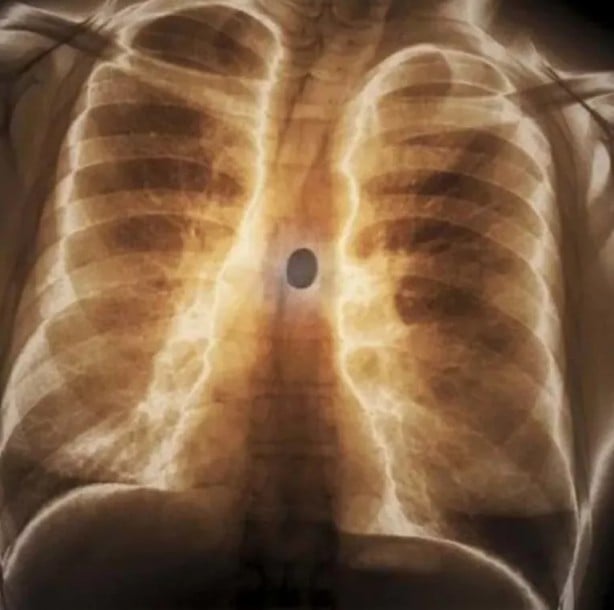

Göğüs kafesinde kurşun olan bir hasta...